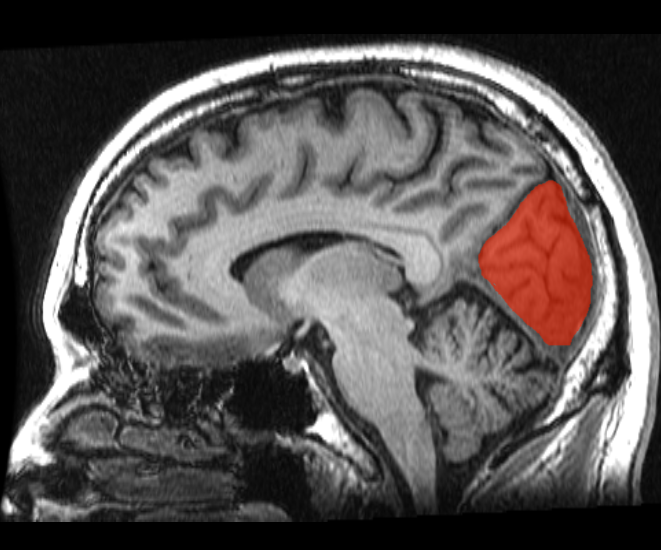

le Cuneus est une région du cerveau dans le lobe occipital.

The cuneus is a portion of the human brain in the occipital lobe. The cuneus (Brodmann area 17) receives visual information from the contralateral superior retina representing the inferior visual field. It is most known for its involvement in basic visual processing. Pyramidal cells in the cuneus (striate cortex) project to extrastriate cortices (BA 18,19).